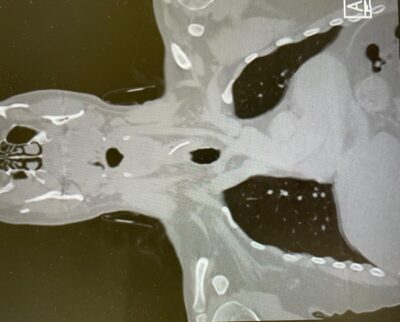

"חיים הגיע אלינו ביום שישי לקראת הצהריים, לאחר שהסתובב שלושה ימים עם תחושת דקירה בבליעה", מספרת ד"ר אור שטריקמן, מתמחה בכירה במחלקת אף אוזן גרון בשערי צדק בניהולו של פרופ' ג'אן איב-סישל . "בשל הרקע של אכילת דג, החשד הראשוני היה שמדובר בעצם תקועה", אומרת ד"ר שטריקמן. "עוצמת הכאב ומשך הזמן שעבר מאכילת הסנדוויץ' היו חריגים, ולכן ביצענו בדיקת CT שהדגימה את הגוף הזר בוושט העליון", מתאר ד"ר אוהד כהן, רופא בכיר ואחראי תחום ניתוחי מיתרי קול וגרון במחלקה.

אולם, החשד הראשוני התבדה כאשר בניתוח הדחוף שנעשה בהובלת ד"ר כהן וד"ר שטריקמן, בליווי של רופאי מרדימים, התברר שהעצם הזר שבלע חיים הוא ברזל חד מאוד באורך של שלושה ס"מ. "ביצענו ניתוח אנדוסקופי דרך הפה, שלפנו את הברזל שכבר הספיק לגרום לפצע בדופן הוושט. חשוב להבין שכל איחור נוסף היה עלול להוביל לזיהום קשה ולסיבוכים", מוסיף ד"ר כהן.